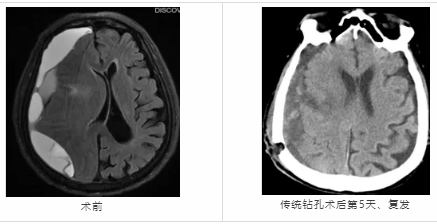

近日,隨州市中心醫(yī)院神經(jīng)外科成功為一名73歲慢性硬膜下血腫顱骨鉆孔引流術(shù)后復(fù)發(fā)患者實施神經(jīng)內(nèi)鏡下小骨窗慢性硬膜下血腫清除術(shù),患者術(shù)后恢復(fù)良好。 73歲的H大爺,十天前無明顯誘因開始出現(xiàn)頭痛、頭昏,伴惡心, ...